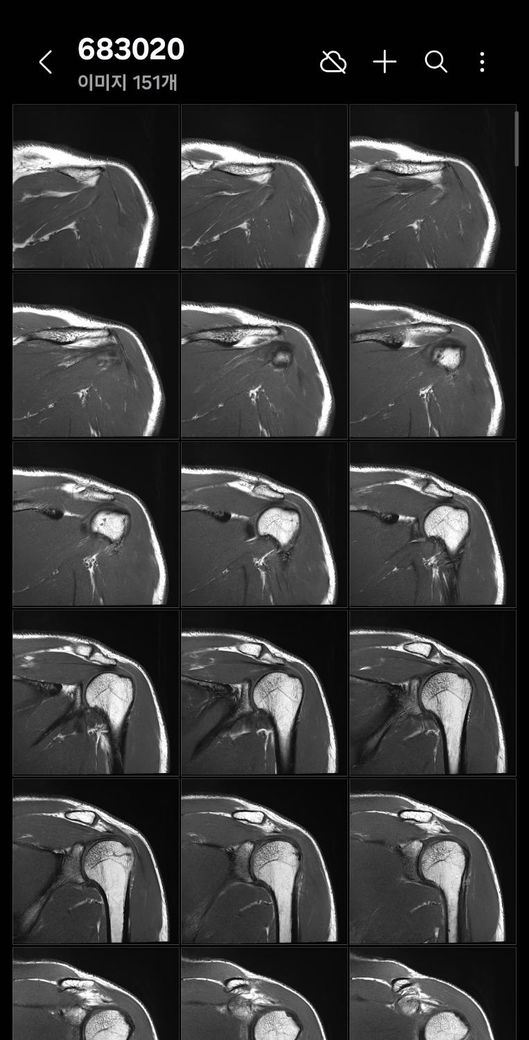

어깨 mri 전문의 소견 부탁드립니다

얼마전에 축구하다가 넘어지고 그날 저녁부터 팔이 안올라가서 건협가서 mri 찍었습니다.

회전근개 파열이 있는지, 없다면 지금 상태가 어떤상태인지와 웨이트 운동 가능할정도의 회복기간이 궁금합니다

• 5번 째 사진

• 6번 째 사진

• 7번 째 사진

Mri에서 별다른 이상소견이 없는 경우 일시적으로 발생하는 움직임이나 기능의 제한일 수 있습니다.

약 2주 이내의 회복기간이 소요될 수 있으며, 현재 mri 사진에서 보이는 염증 소견은 타박상으로 인해서 발생하는 것일 수 있습니다.

별다른 파열의 징후는 보이지 않습니다.

질문하신 내용 잘 읽어보았습니다. MRI결과에서 회전근개 파열 여부가 핵심입니다 부분 파열과 염좌라면 보존적 치료후 6~8주 내 웨이트 복귀 가능하지만 완전파열이면 수술 후 최소 3~6개월 재활이 필요합니다. mri 판독 결과지를 확인해야 정확한 상태와 회복 기간을 판단할 수 있습니다!